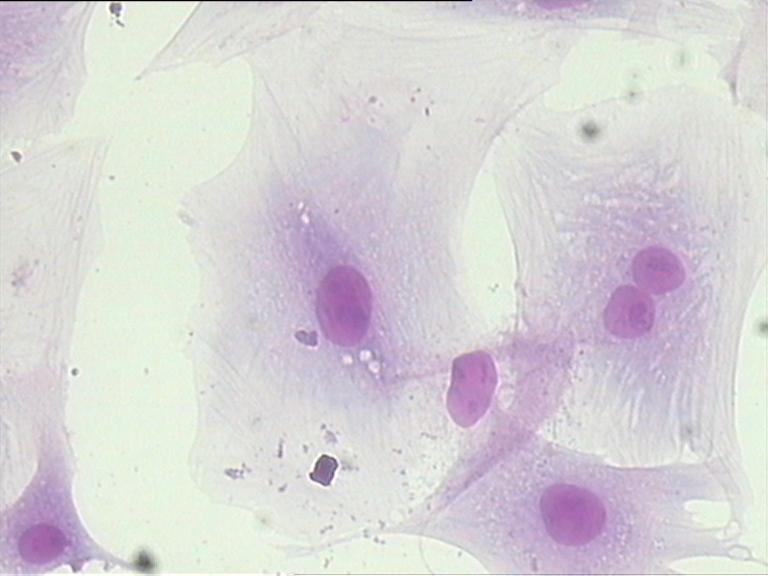

細胞傳代

細胞凍存和復蘇

細胞劃痕

細胞侵襲、轉染